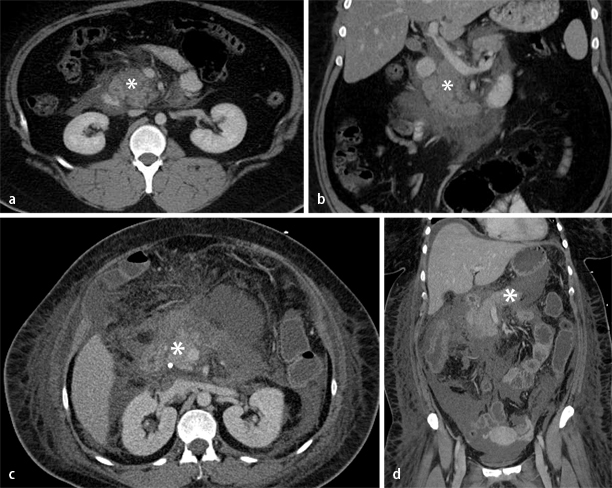

Kontrastmittelverstärkte Computertomographie

Obwohl die kontrastmittelverstärkte Computertomographie (KM-CT) eine der sensitivsten Methoden zur Detektion von Pankreasnekrosen ist (Abb. 1), ist von dem unkritischen Einsatz in der Frühphase der akuten Pankreatitis dringend abzuraten. Zum einen ist diese Methode für die eigentliche Diagnosestellung (klinische Symptome plus Lipaseerhöhung plus ggf. Sonographie) nicht nötig; zum anderen lassen sich Nekrosen in den frühen Krankheitsstadien auch in der KM-CT noch nicht abgrenzen (frühester sicherer Nachweis nach 48–72 h). Auch vor dem Hintergrund einer potenziellen Verschlechterung der Nierenfunktion bei schwerer Pankreatitis durch die Kontrastmittelgabe muss bei

Bei der Indikationsstellung muss die klinisch-therapeutische Konsequenz diskutiert werden

der Indikationsstellung für eine KM-CT immer die klinisch-therapeutische Konsequenz diskutiert werden. Mögliche Indikationen für die Durchführung einer KM-CT ergeben sich somit in erster Linie zur Darstellung von Komplikationen mit ggf. therapeutischer Konsequenz. Hierzu gehören superinfizierte Pseudozysten , die einer Drainageanlage bedürfen, aus differenzialdiagnostischen Erwägungen bei unsicherem klinischem Bild, fehlender Besserung, neu aufgetretenem/progredientem Organversagen oder Entwicklung einer Sepsis .